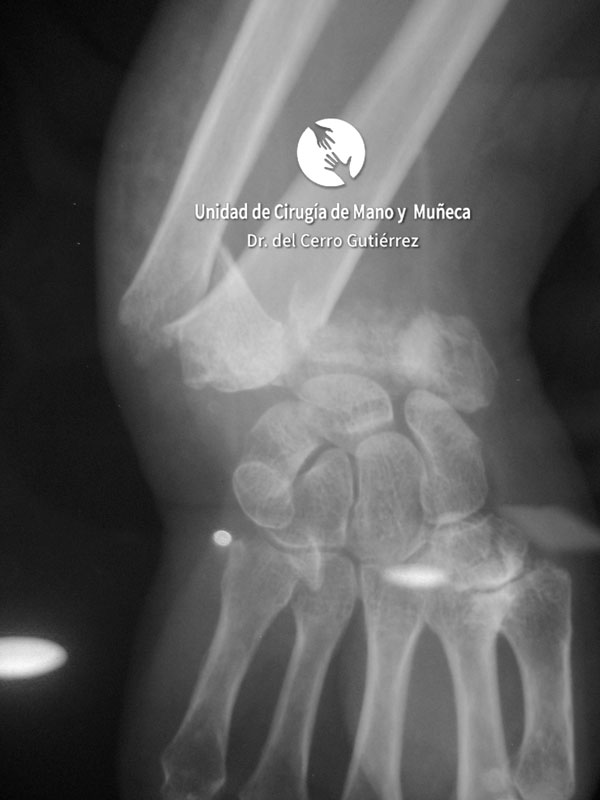

Imágenes de diagnótico de fracturas del radio distal de la muñeca

Las imágenes de diagnóstico son fundamentales para evaluar las fracturas del radio distal, identificar su gravedad y definir el tratamiento más adecuado. A continuación, presentamos una serie de ejemplos que muestran diferentes tipos de fracturas.

Fractura del Radio. Desplazamiento Dorsal.